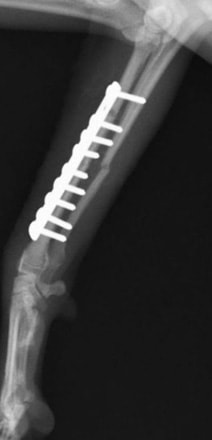

両前肢の骨折:橈骨尺骨骨折整復手術①

<右前肢>

![]() 来院時の右橈骨尺骨骨折のレントゲン写真 |

![]() 手術後のレントゲン写真 |

手術写真です。骨折端を露出させ、骨折端を合わせて、プレートとスクリューにて固定します。 |